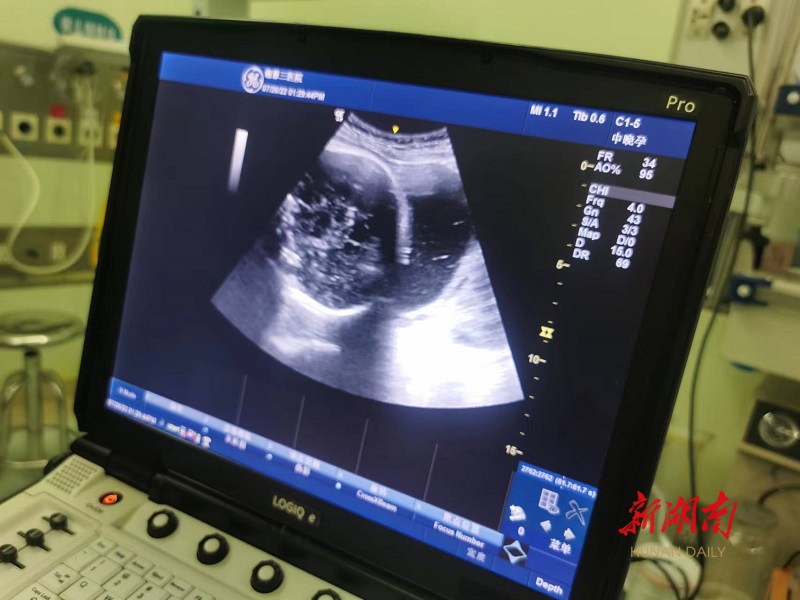

(术后B超提示头位。)

在该院产科主任米春梅指导下,产科副主任医师王楠在B超的监护下,经腹壁用手转动胎儿,使不利于分娩的胎位转为有利于阴道分娩的头位。术中超声实时监测胎位及胎心,术后孕妇无腹痛、阴道流血、流液等不适,胎心监护一切正常,孕妇全程无痛感,目前已顺利出院。